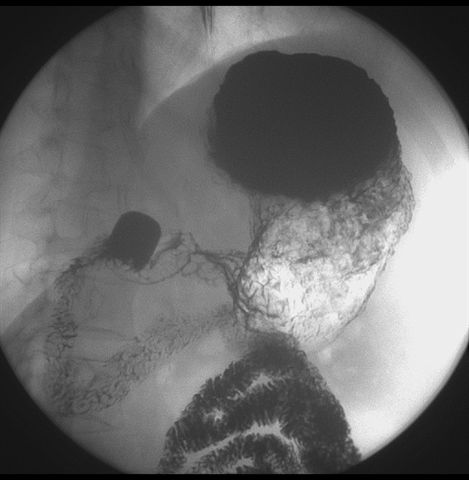

标题: X6872:F,69y,胃部不适。

胃窦至幽门段胃壁僵硬,扩张受限,局部纠集粘破坏,呈杵状。提示溃疡癌变可能性大。

胃窦癌可能性大,建议胃镜活检。钡剂太稀,吃的有点多。

支持考虑胃窦癌可能,胃内滞留液太多,胃窦部僵硬。

胃窦部见钡池影,局部粘膜紊乱,纠集呈杵状改变,胃壁扩张受限,胃窦癌可能性大,建议胃镜检查.

胃窦部管腔扩张度较差,形态略有改变,胃窦粘膜显示欠佳,胃窦部占位可能性大,结合胃镜活检。

胃窦部狭窄、稍僵硬,考虑胃窦癌?建议胃镜检查。

北京肿瘤医院胃镜诊断皮革胃。